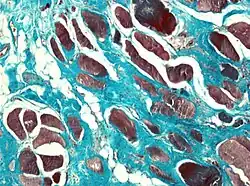

Muscle biopsies are also a useful tool to diagnose camptocormia. Muscle biopsies found to have variable muscle fiber sizes and even endomysial fibrosis may be markers of bent spine syndrome. In addition, disorganized internal architecture and little necrosis or regeneration is a marker of camptocormia.

Myopathic origin BSS can be secondary to various muscular disorders or occur as a primary idiopathy.[2] These etiologies are termed secondary and primary BSS respectively. Idiopathic primary BSS is a late-onset myopathy with progressive muscular weakness that is detected on the spinal extensor muscles in elderly patients and is more predominant in females.[2] The pathogenesis of primary BSS is typically related to fibrosis and fatty infiltration of muscular tissues and to mitochondrial changes due to the aging process.[2] Specifically, weakening occurs in the paravertebral muscles of patients. These paravertebral muscles have a great influence over the walking stance and gait of a patient, so fatty infiltration and degradation of these muscle lead to the characteristics that easily define BSS, such as the anterior flexion of the back combined with an ability to keep upright with any kind of support (e.g., holding onto a table).[4]